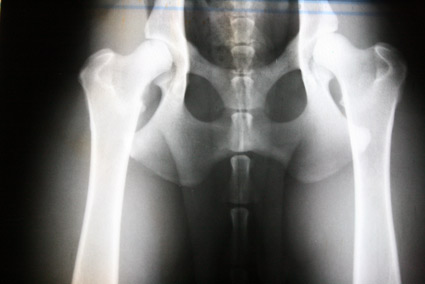

Hier nun einige HD Röntgenbilder:

HD frei / HD- A / HD-0 / HD-normal |